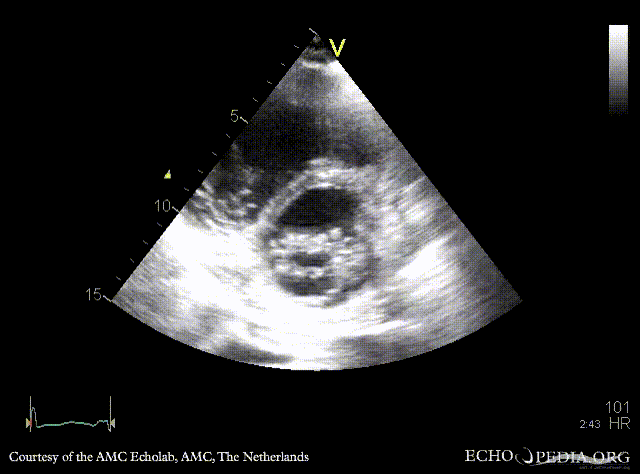

E00452.gif E00453.gif

PSAX: flattening of IAS, enlarged right ventricle PSAX: prolaps of PMVL